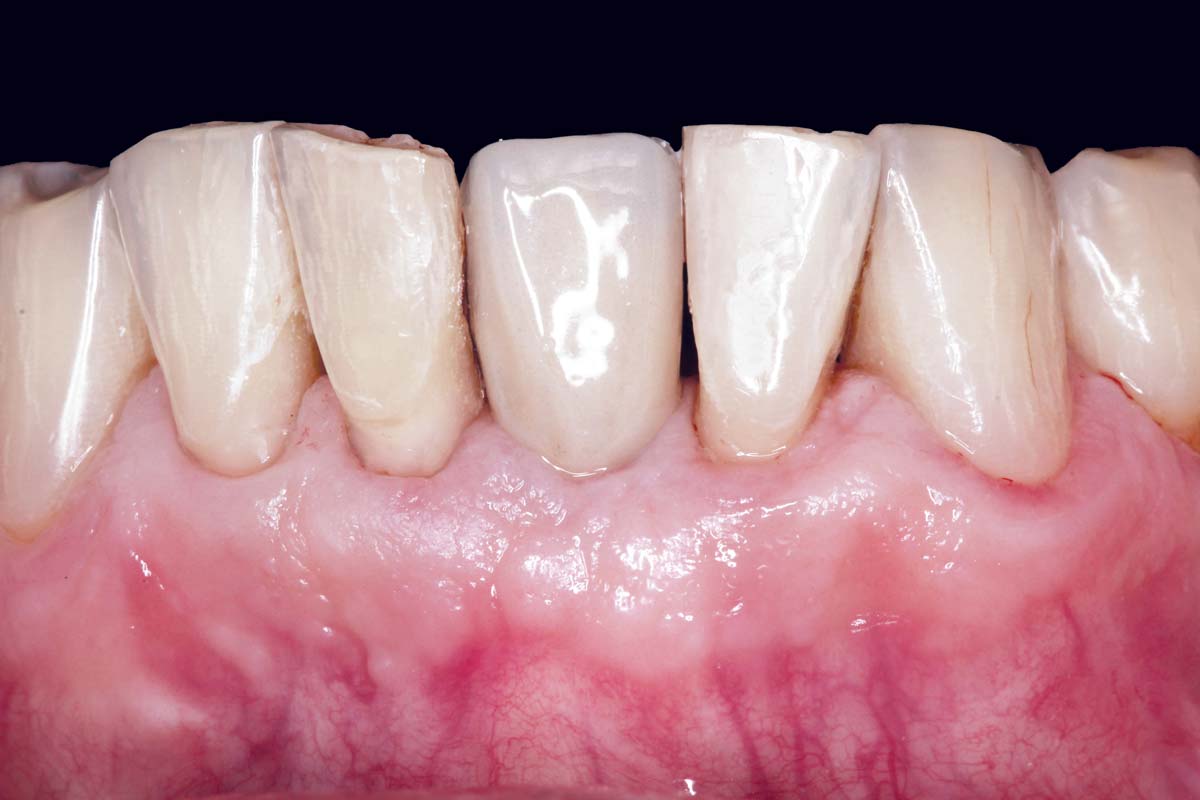

Initial view of the case. Discoloration of 1.1 and mild class I gingival recession